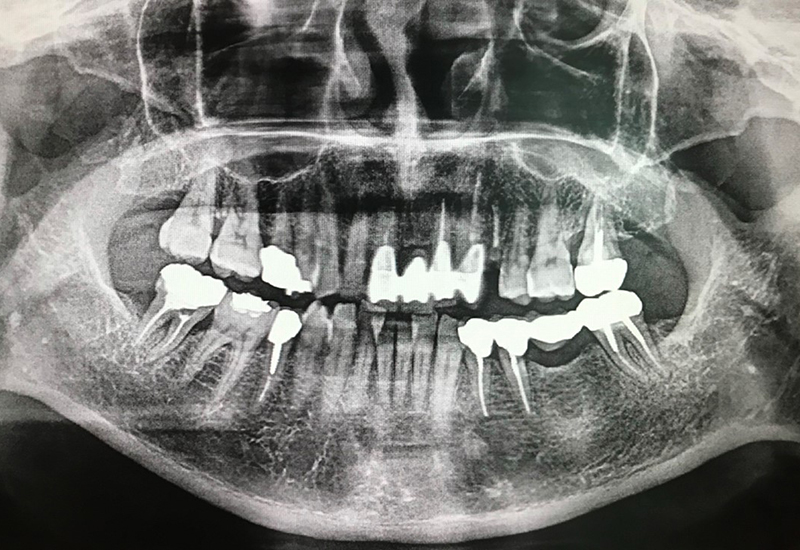

治療前 |